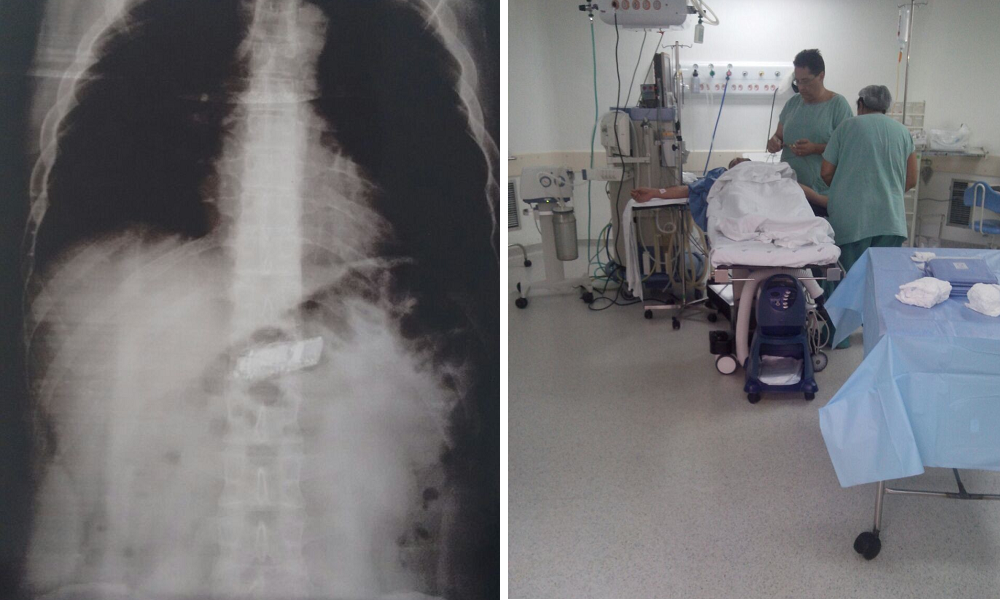

Um presidiário passou por uma cirurgia depois de ser flagrado com um pequeno celular dentro do estômago. O caso aconteceu na Penitenciária de Mairinque, região metropolitana de Sorocaba.

V.A.L.P foi flagrado no último dia 4 por agentes que desconfiaram de seu comportamento durante uma revista de rotina. Levado à unidade hospitalar, confessou o crime depois que o exame de raio-x revelou a presença de um pacote plástico. Segundo informações da Secretaria da Administração Penitenciária (SAP), ele foi operado no último sábado (7) e voltará para a prisão depois da recuperação.